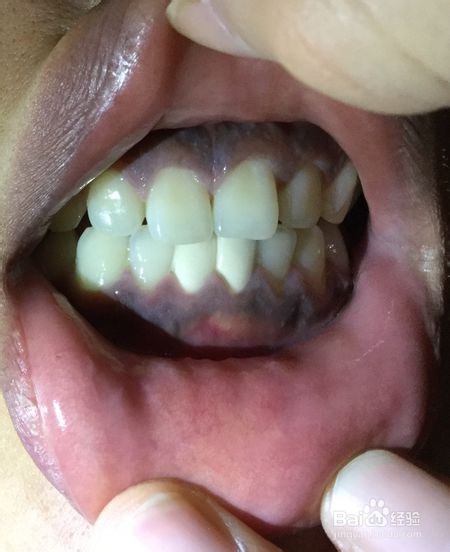

2、临床上将牙龈组织分为游离龈、附着龈和龈乳头三部分。正常人的附着龈呈粉红色,而有少数正常人在附着龈的表面则可以见到有弥散的云雾状的黑色素的沉积,特别是在肤色较黑和黑种人中多见。这种色素沉着没有病理意义,也无需治疗。普遍少数龈缘发黑是牙结石导致的,定期洗牙即可。